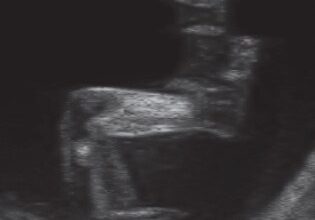

Ecografía de 14 semanas: empieza el segundo trimestre. El cordón umbilical tiene tres vasos sanguíneos, dos arterias y una vena. Se puede ver la circulación de estos vasos.

Todas las estructuras básicas del cuerpo, tanto por dentro como por fuera, ya están formadas, aunque en miniatura. Tu bebé mide unos 9 centímetros. Tiene ahora, más o menos, el tamaño de un limón amarillo.

El cuerpo está creciendo ahora con más rapidez que la cabecita. Ya se puede ver el cuello. Al final de esta semana los brazos se habrán alargado y se verán proporcionados con el resto del cuerpo. Si lo vieras de cerca notarías que le está apareciendo por todo el cuerpo un vello muy finito que se llama lanugo.